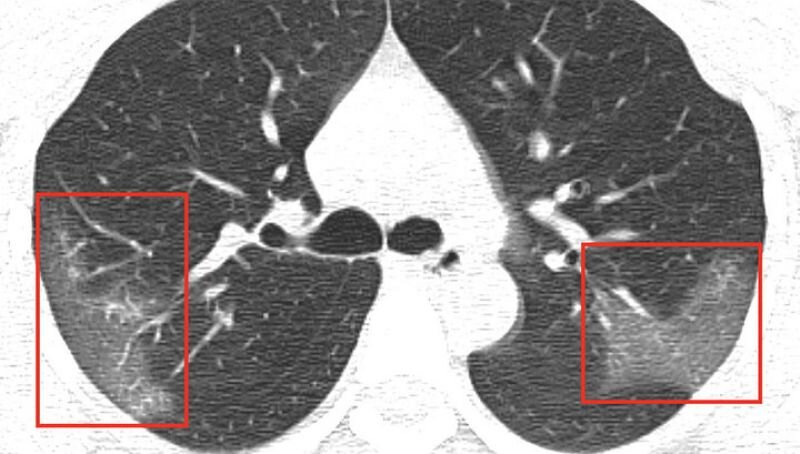

Потом температурила нормализовалась но усталость осталось. Меня хотели выписывать но я сходил на КТ и результат меня поразил.

У меня была двух сторонняя пневмония. КТ показало 75% поражения!